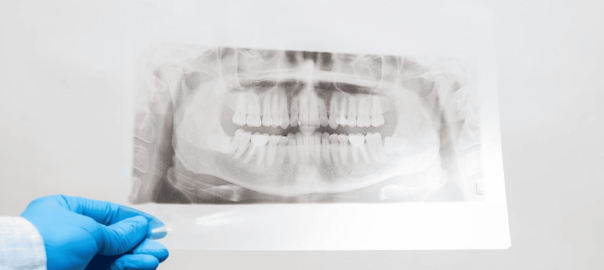

インプラントで歯がない期間はどのくらい?治療の流れと対処法

インプラント治療は数ヶ月の期間を経て、複数の治療ステップを進める治療法です。 その間には歯がなくなる期間があるため、見た目や生活の質などを考える方は悩みの種になるのではないでしょうか。 しかし、歯がなくなる期間には仮歯を … 続きを読む インプラントで歯がない期間はどのくらい?治療の流れと対処法